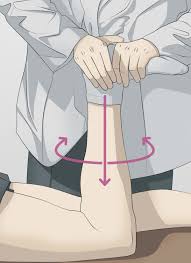

Ο εξειδικευμένος Ορθοπαιδικός θα μπορέσει σχετικά εύκολα να διαγνώσει την κάκωση από την κλινική εξέταση και μόνο. Η ευαισθησία στην ψηλάφηση του διαστήματος μεταξύ μηρού – κνήμης αποτελεί ένα σημαντικό σημείο. Ειδικά tests όπως το McMurray και το Appley test (εικόνα 3 )

σχεδόν πιστοποιούν το πρόβλημα. Σχεδόν πάντοτε, θα ζητηθεί η διενέργεια μαγνητικής τομογραφίας γόνατος η οποία θα περιγράψει με λεπτομέρεια τη ρήξη και τις πιθανές συνοδές κακώσεις (εικόνα 4 . Η εκτίμηση της θέσης και έκτασης της βλάβης είναι πολύ σημαντική για τη θεραπεία, καθώς περιφερικές ρήξεις (δηλαδή στην εξωτερική πλευρά του μηνίσκου) χωρίς επέκταση στην ελεύθερη επιφάνειά του, άνω ή κάτω, έχουν δυναμικό ίασης λόγω της επαρκούς αιμάτωσης αυτής της ζώνης.